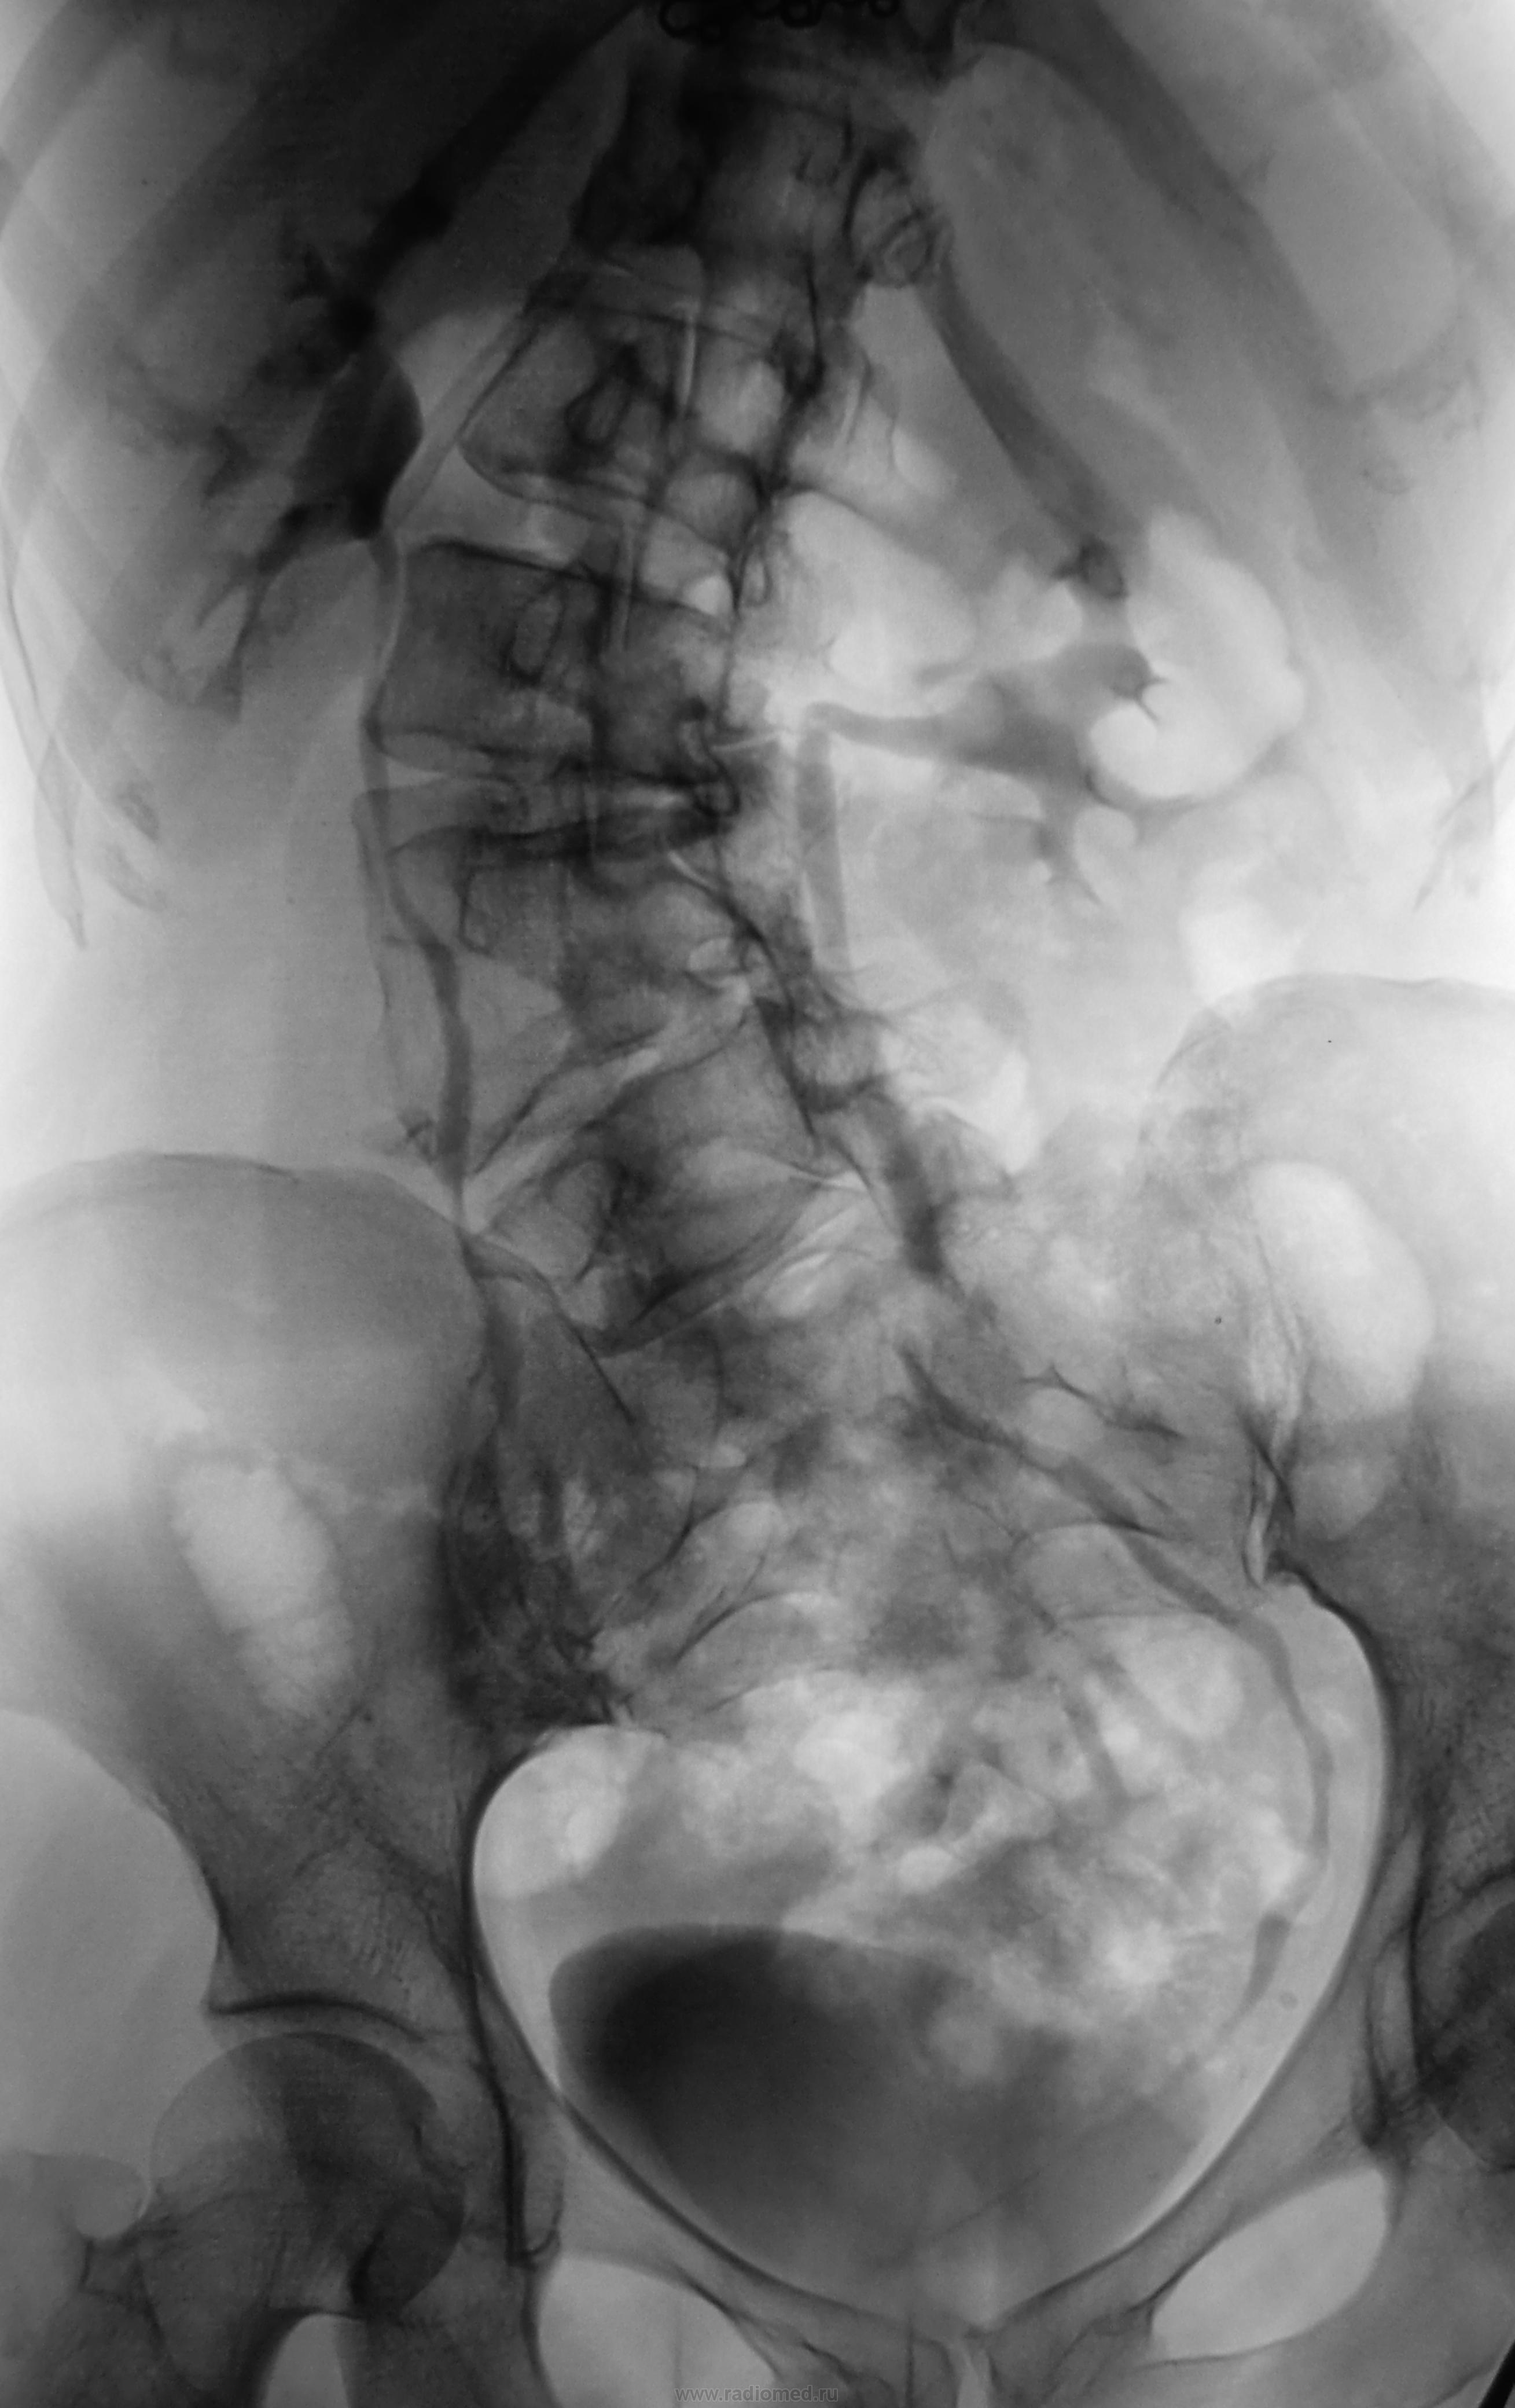

Урогрофия удалась, патологиии я не выяввил.

Однако на топографических проблемах и перегибе практически под прямым углом ЛМС слева акцентировать внимание не помешало бы))))

Я, наверное, придираюсь, но справа шейки чашечек выглядят спазмированными.

Насчет спазма шеек чашечек не знаю))), но вот левый мочеточник (даже при измененных соотношениях) впадает в пузырь как-то справа. Интересно, что хотели доктора от в/в. Может, это демонстрация аномалии позвоночника?

Просто это прекрасный наглядный пример, чем чреват сколиоз)))

имхо: Можно предположить, что получается так проекционно, по причине сколиотической деформации( таз как бы ротируестя в фронтальной плоскости по часовой стрелке; не исключается вариант и дистопии устья правого мочеточника.

Пациентка обследуется в областной онкологической "конторе" по поводу рака шейки матки. Вот они, чтобы себя не утруждать и направляют пациентов "дообследоваться" по месту жительства.

Этой пациенте из областной конторы было назначено ОГК, ЖКТр, ирригоскопия и внутривеная урография.